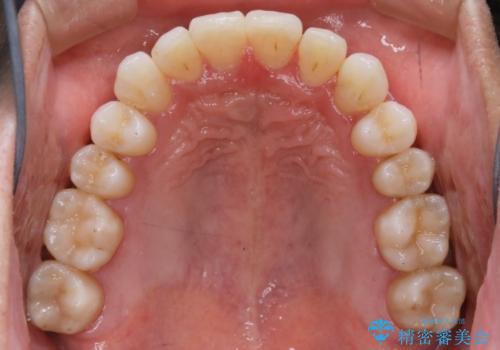

【非抜歯】八重歯を治す マウスピース矯正

- 前歯のガタつきの治療を主訴にご来院されました。

目立たない装置をとのご要望があったため、検査結果をふまえてインビザラインでの非抜歯矯正を行うこととなりました。

非抜歯での治療

抜歯をせずに歯のガタつきを治すためのスペースを作るために

①歯の遠心移動

②歯列弓の拡大

③IPR(歯を少し小さく削る)

この3つの方法を複合的に組み合わせて治療を行いました。

抜歯をせずとも笑った時の歯の見え方が劇的に変化していることが分かります。